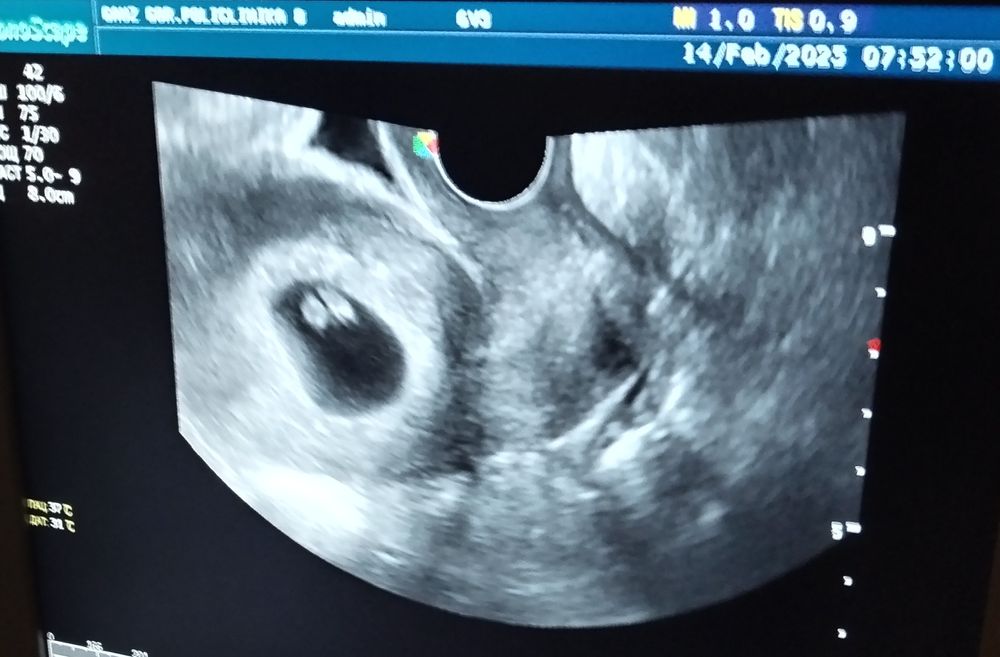

Была на узи 10 числа . Показал одного эмбриона , желточный мешок особо было не видно . ( в платной больнице)

Вчера было плановое узи в госке и появилось второе пятнышко , не в виде обручального кольца ( как желточный мешок , в в виде такого же пятна как эмбрион ) подскажите что может быть? Может ли быть второй эмбрион .

А что не понятного, вроде бы все ок. Отстает срок от акушерского, но так бывает, в процессе будет понятно. ЖМ не всегда визуализируется, это не страшно. Эмбрион один, узист бы точно рассмотрел, если бы было два.

Eliza, так если вы все понимаете , что желточный мешок то не увидели? Он по описанию врача внизу , сверху эмбрион

Ангелина Ситнова, я неправильно выразилась. Имела ввиду, что не всегда ЖМ визуализируется в виде кольца.

Просто эмбрион уже большой и «отлипает» от желточного мешка. Он совсем рядом с ним только на маленьком сроке, потом может отдаляться. У вас всё хорошо по УЗИ.